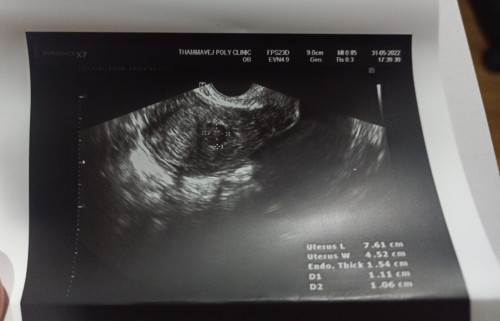

สอบถามประสบการณ์แม่ ๆ ค่ะ..เจอแบบนี้ในมดลูก คือ ถุงตั้งครรภ์ใช่ไหมคะ #ขอบคุณสำหรับคำตอบค่ะ